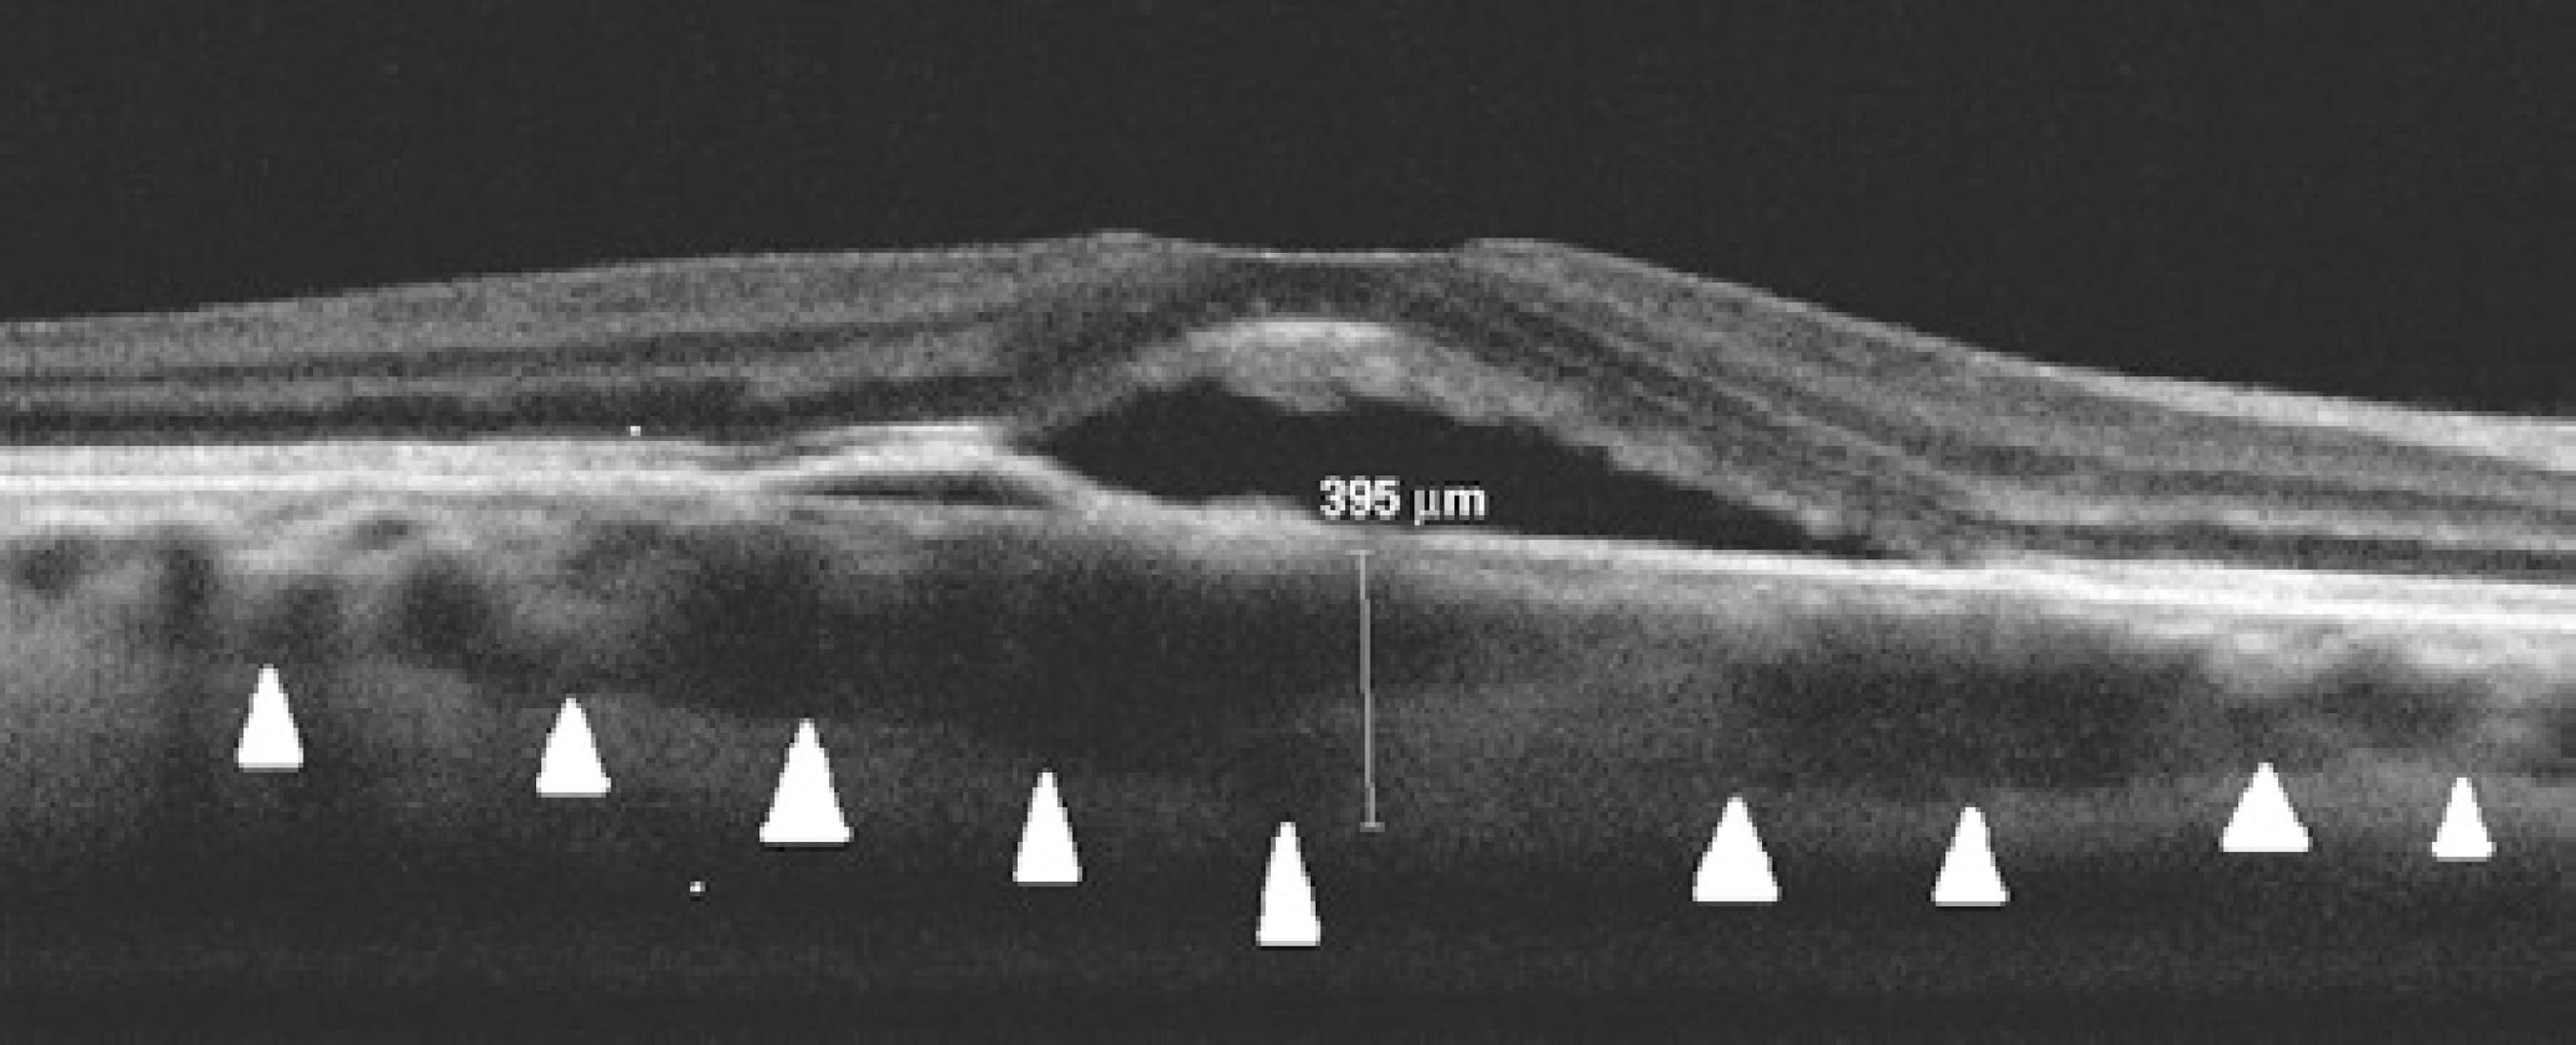

Figure 1 Baseline enhanced depth imaging spectral-domain optical coherence tomography imaging of a patient with acute central serous chorioretinopathy. The subfoveal choroidal thickness was 395 μm.

The mean SFCT and the mean BCVA at baseline and the final visits for both groups are summarized in table 2. Figures 1 and 2 show a representative case at the baseline and final visits, respectively. All patients showed complete resolution of neurosensory detachment and improvement in vision at the final visit after the follow-up period. In the IVB group, the mean SFCT was 315 ± 57 μm at the baseline visit, which decreased to 296 ± 53 μm at the final visit after a mean follow-up period of 10.2 months. In the control group, the mean SFCT was 307 ± 51 μm at the baseline visit, which decreased to 266 ± 41 μm at the final visit after a mean follow-up period of 8.4 months. The mean SFCT at the baseline and final visits did not significantly differ between the groups. Although there was a significant decrease in the mean SFCT for the control group, no significant decrease was found for the IVB group (41 vs 19 μm, p=0.003 vs p=0.071). The mean BCVA levels in the IVB group at the baseline and final visits were 0.49 (logMAR 0.37) and 0.70 (logMAR 0.19), respectively. In contrast, the mean BCVA levels in the control group at the baseline and final visits were 0.45 (logMAR 0.39) and 0.86 (logMAR 0.10), respectively. The mean BCVA at the baseline visit was similar for both groups, and the mean BCVA increased significantly in both groups (p=0.001). However, the increase in the mean BCVA was significantly greater for the control group (0.41; logMAR 0.29) than for the IVB group (0.22; logMAR 0.17; p<0.05 for BCVA), and the mean final BCVA of the control group was significantly greater than that of the IVB group [0.86 (logMAR 0.10) vs 0.70 (logMAR 0.19 p<0.05].